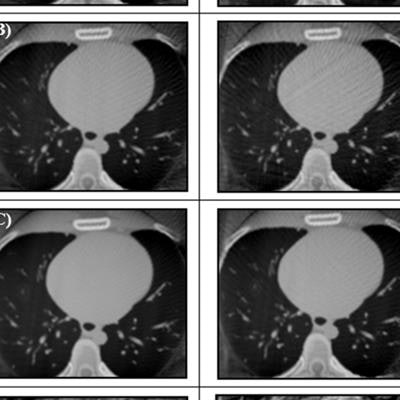

Reconstructed cardiac-gated 3D images for acquisition windows of 60% to 70% through the cardiac cycle for ACROBEAT, with an average of 97 (A), 115 (B), and 146 (C) projections; and conventional multisweep retrospective gated protocol (D) with 95 projections. Image courtesy of Reynolds et al, Phys Med Biol, 10.1088/1361-6560/ab03f4.

Reconstructed cardiac-gated 3D images for acquisition windows of 60% to 70% through the cardiac cycle for ACROBEAT, with an average of 97 (A), 115 (B), and 146 (C) projections; and conventional multisweep retrospective gated protocol (D) with 95 projections. Image courtesy of Reynolds et al, Phys Med Biol, 10.1088/1361-6560/ab03f4.Increasing the acquisition window from 60%-70% to 60%-80% resulted in fewer streak artifacts in conventional retrospectively gated images for the two regular ECG traces but not in the arrhythmic trace. Increasing the window length did not have a detrimental effect on either the C/N ratio or ERW of the ACROBEAT images. For medium and arrhythmic heart rates, the 60% to 80% window significantly reduced total scan time, although it slightly increased scan time for the low heart rate.